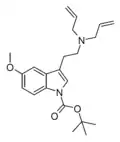

| NB-5-MeO-DALT | artificial | 1-OCOC(CH3)3, 5-OCH3 | H2C=CH-CH2 | H2C=CH-CH2 | 1-(t-butoxycarbonyl)-5-methoxy-N,N-diallyltryptamine | |